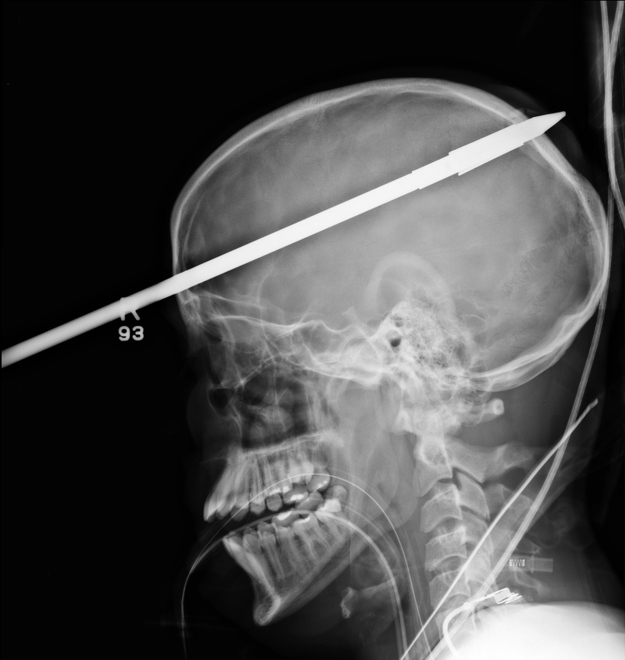

A spear lodged in the skull of a 16-year-old boy. One of the boy’s friends was loading a speargun when it accidentally fired.